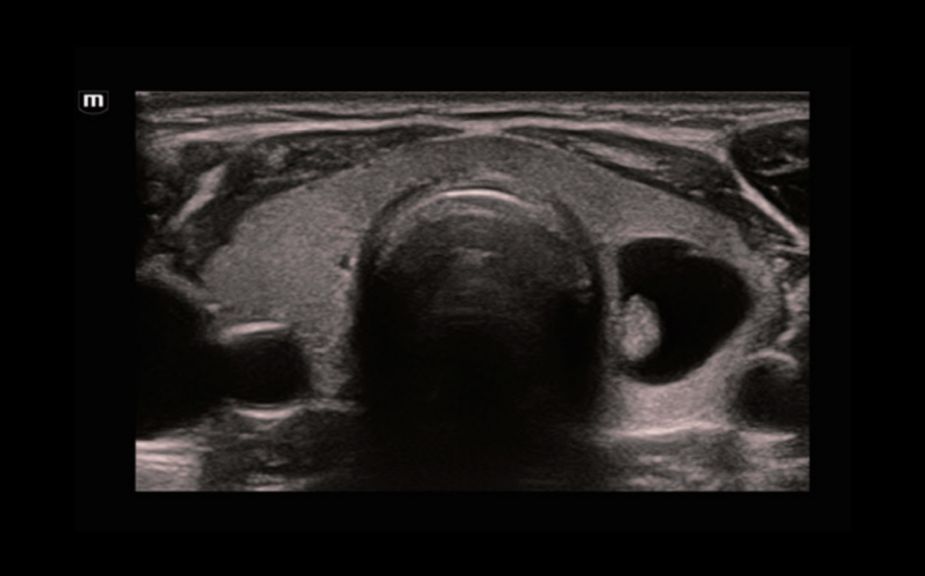

A Novel Approach of Vascular Hemodynamics: V Flow

Kolorowe wektory wskazuj? szybko?? i kierunek przep?ywu kom├│rek krwi. Dzi?ki wysokiej cz?stotliwo?ci od?wie?ania obrazu, V Flow zapewnia niezwykle ?yw?, dok?adn? i niezale?n? od k?ta nachylenia bramki dopplerowskiej wizualizacj? z?o?onych przep?yw├│w hemodynamicznych w naczyniach.

V Flow

A Novel Approach of Vascular Hemodynamics: V Flow

Kolorowe wektory wskazuj? szybko?? i kierunek przep?ywu kom├│rek krwi. Dzi?ki wysokiej cz?stotliwo?ci od?wie?ania obrazu, V Flow zapewnia niezwykle ?yw?, dok?adn? i niezale?n? od k?ta nachylenia bramki dopplerowskiej wizualizacj? z?o?onych przep?yw├│w hemodynamicznych w naczyniach.

V Flow